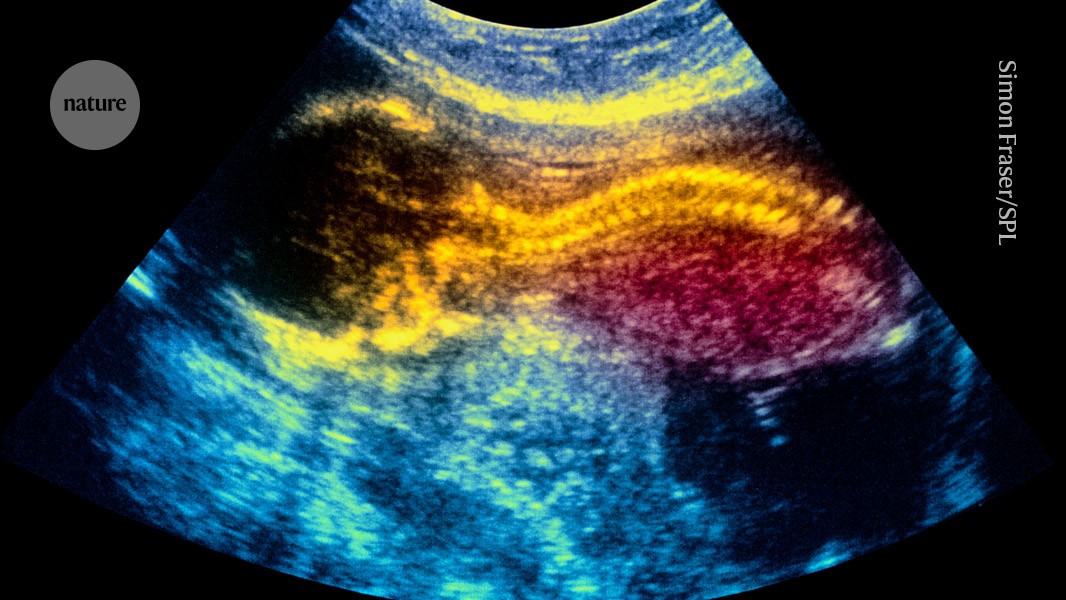

An in utero treatment using placenta-derived stem cells could treat infants with a neural-tube condition called spina bifida. Credit: Simon Fraser/Science Photo Library

Stem cells applied to the exposed spinal cords of fetuses in utero could…